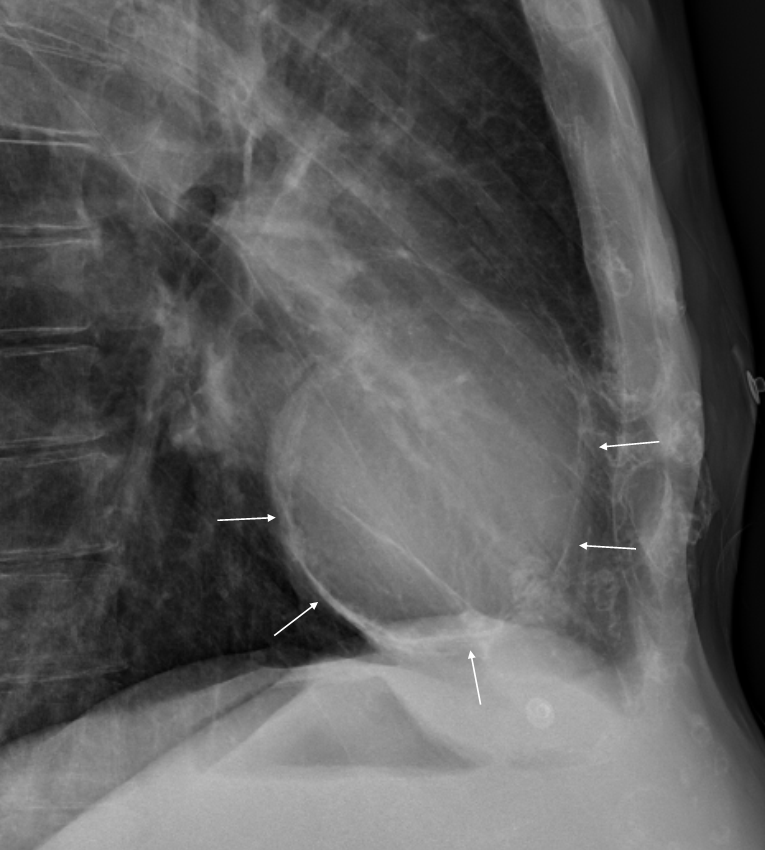

RiT radiology Pericardial Effusion on Lateral Chest Radiograph

Pericardial Effusion Lateral Chest X-Ray . — lateral cxr of pericardial effusion. — pericardial effusion is present when the fluid in the pericardial space exceeds its physiological amount (≤50. — the initial approach in a patient presenting with pericardial effusion includes personal and family medical history,.